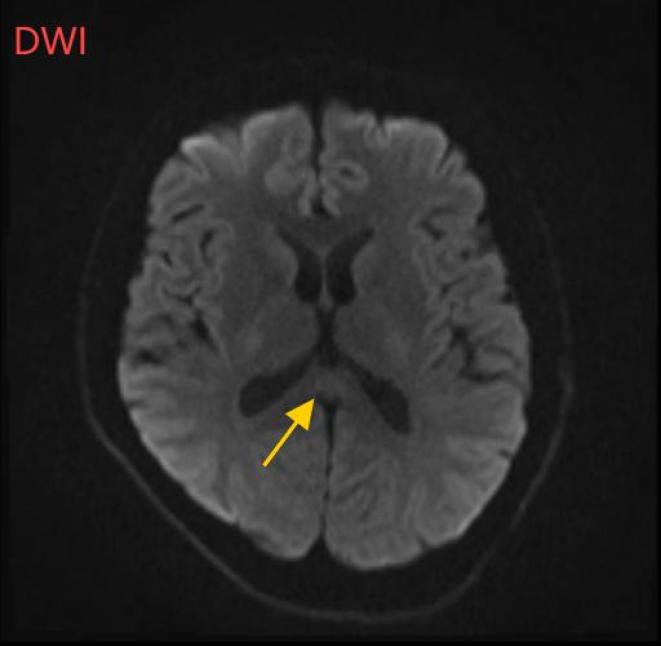

医生摇摇头。经过头部磁共振平扫、弥漫、增强图像等检查。,医生诊断,小董患有一种罕见的疾病:可逆性体压部综合征。

根据小董的影像数据,受压部位发生病变。